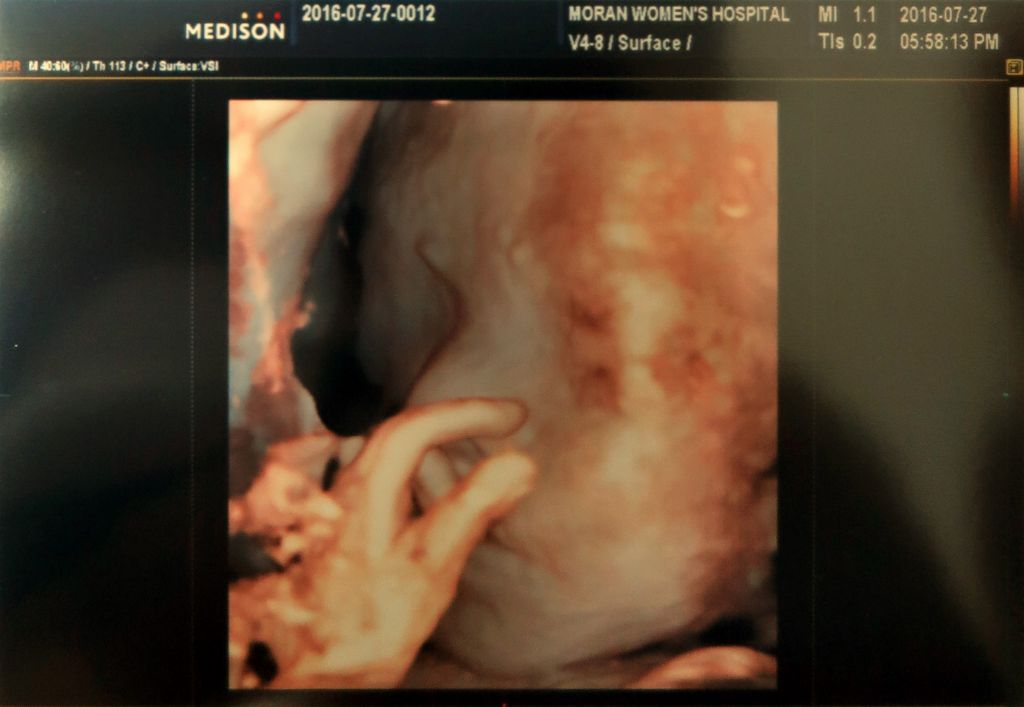

지난주 수요일에 별이 보러 병원에 다녀왔습니다. 초음파로 확인 할 수 있는 안에서는 아주 건강히 잘 자라고 있답니다.^^ 요즘은 제법 태동도 느낄 수 있는데 아빠가 만지면 움직이다 멈춰서.ㅠ 삐짐입니다.ㅋㅋ 이번에는 초음파 동영상의 BGM을 바꿔보았습니다. 지난번에 콘서트 다녀왔던 장범준 2집에 실려있는 『사랑에 빠졌죠 (당신만이)』 입니다. 3D 초음파로 얼굴 찍었는데 누굴 닮아서 낯을Read More →